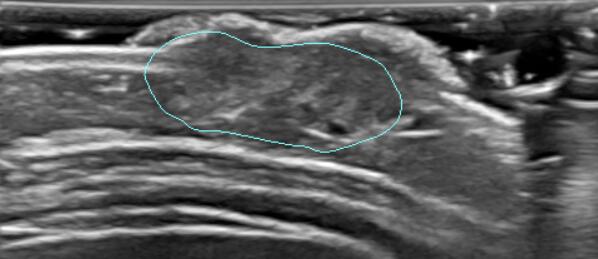

模型:一开始使用 unet++ 进行模型训练,但是效果不是很满意,后面使用使用 deeplabv3+ 模型完成了血管瘤图像的训练,在比赛中取得了 dice=88.6 的成绩,位列第十。

同时完成了相关的接口,在远程服务器上测试观感较好。以下是对一张图片进行的分割预测结果

完成模型的训练,使用 deeplabv3+ 模型比较好的完成了比赛(rank10),并且完成了项目使用此模型的相关接口

收获一次比赛的经验,顺利的通过了测试并且取得了还不错的分数。总共训练了 1000 个 epochs,但是从 500epochs 后继续训练,提升效果甚微。后面打算用 mobilenet 来做 backbone 看看,结果是否会更好。最近 transformer(attention is all you need)比较火,从 NLP 破界到 CV,在不用传统 CNN 和 RNN 的基础上对于图像的全局感受有了更好的效果。学习的过程中,我也看到了一篇跟 transformer 相关用于医疗图像分割的文章,swin-transformer,打算后期尝试能不能用它达到一个更好的效果。